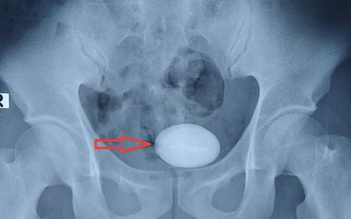

Hy hữu: Quên ống thông 5 năm trong niệu quản, sỏi bàng quang to như trứng ngỗng